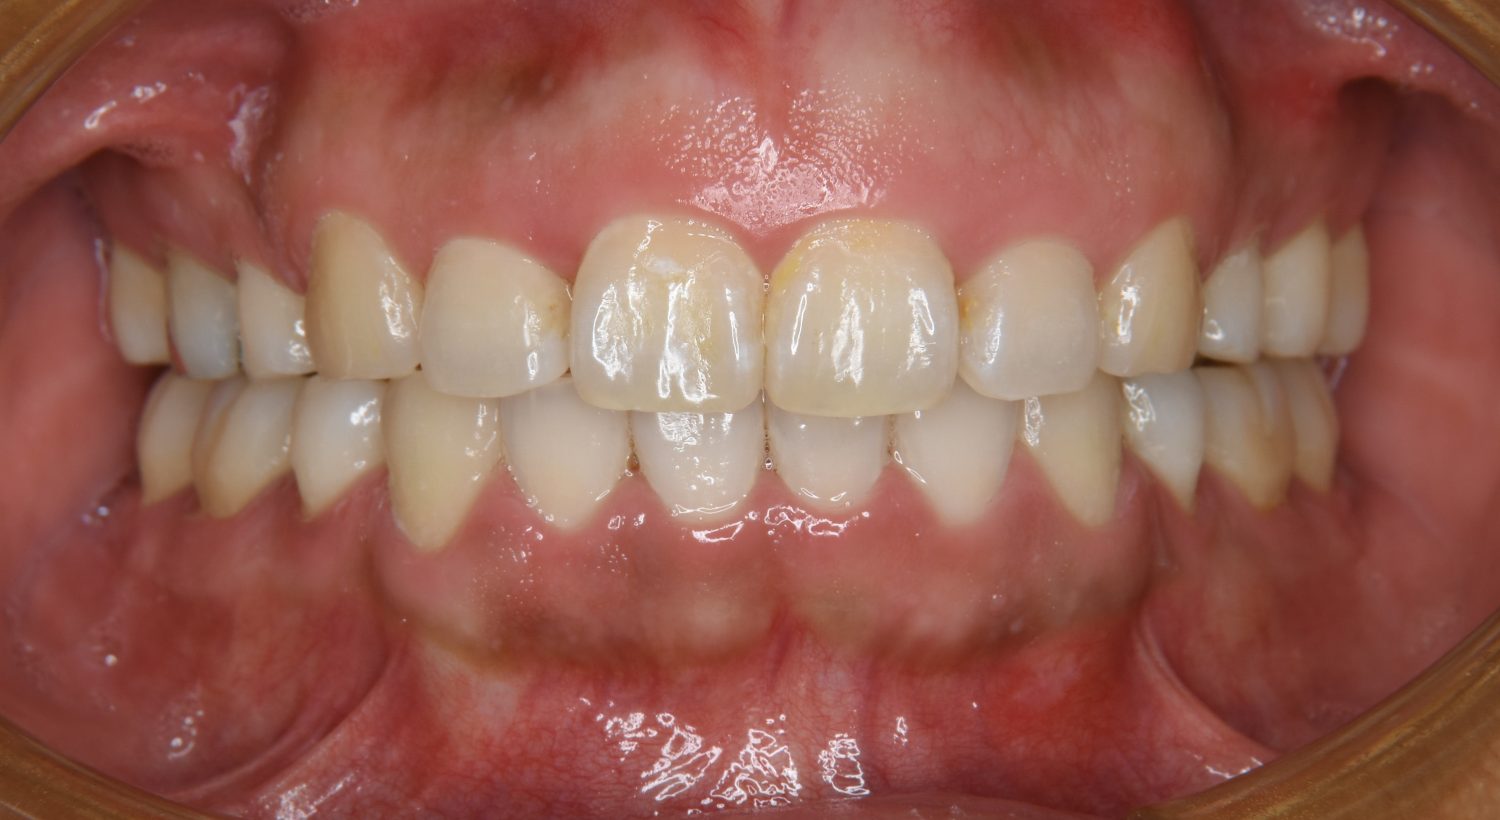

叢生の症例紹介②

Before

主訴

歯の凸凹を治したい。

治療内容

アライナー(インビザライン)にて非抜歯で治療を行いました。

治療費

1,150,000 円(税込)

治療期間

26ヶ月

通院回数

14回

想定されたリスク

※歯根吸収、歯肉退縮、歯髄壊死、顎関節症状

※アライナー(インビザライン)は日本の薬機法未承認の矯正装置であり、医薬品副作用被害救済制度の対象外となる場合があります。

上下前歯部に叢生(凸凹)が認められる状態でした。歯列の遠心移動を行うことで機能面および審美面が改善されました。